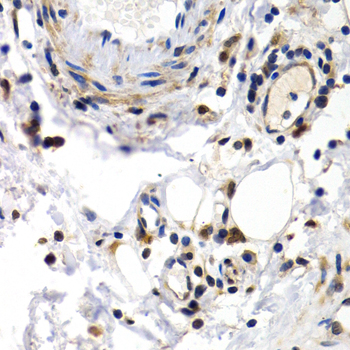

Immunohistochemistry of paraffin-embedded human normal colon using PKLR antibody at dilution of 1:200 (400x lens).